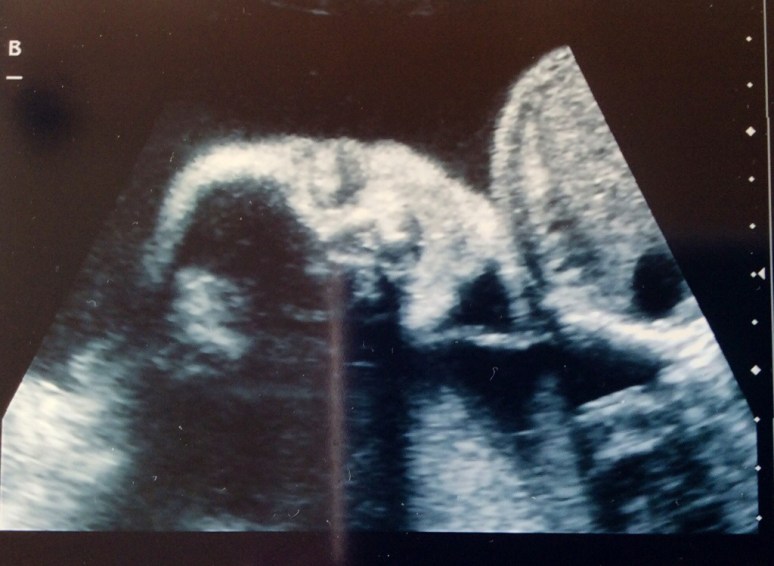

Monday we had our fetal echo and it looks like both babies hearts are just fine. Sigh of relief! Baby A still has her small calcification, but the radiologist was not concerned at all and said not to worry. We also had another growth check at this same ultrasound appointment. Baby A is estimated to be 1 lb 14 oz and Baby B is estimated to be 2 lbs. Baby A is in the 67th percentile and Baby B is in the 83rd percentile. They are growing and we couldn’t be happier!

Baby B Frontal View #1

Baby B Frontal View #2